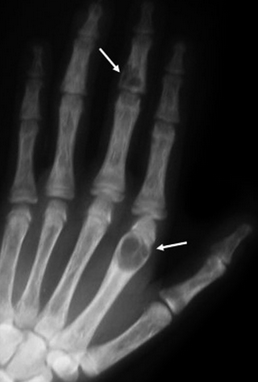

A 44 year old male presents to the ED after getting in a gang fight. He says he was hit just above the elbow with a baseball bat. His x-ray is shown below. What motor tests could you do to assess if nerve damage has also occurred?

The median nerve is subject to injury in this case. You could test thumb abduction, extension and opposition. You could also test wrist flexion and flexion of the index and middle fingers. You should also test for sensory deficit in the distribution of the median nerve.